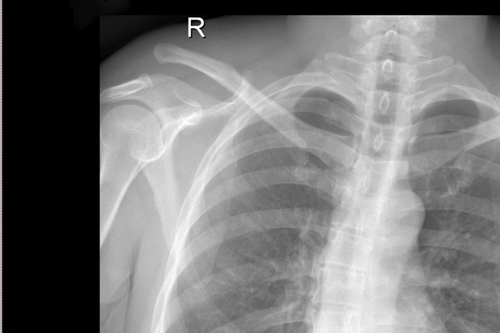

术前DR